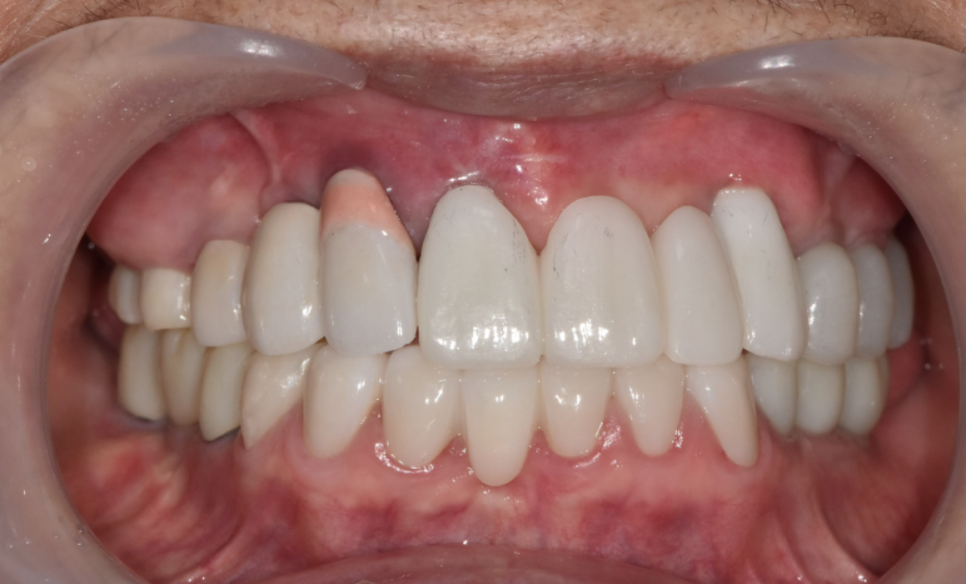

결과적으로,

아래 앞니 7개는 크라운으로 살리고,

총 12대의 임플란트를 더 식립하여

임플란트 보철로 수직 고경을 다시 세우는 방식으로

전체 교합을 재구성했습니다.

240510

치료가 마무리된 뒤

환자분은 거울을 보시더니

“전에는 입이 쏙 들어가 보였는데

이제는 괜찮아 보여요”

라며 환하게 웃으셨습니다.

230211 (전) 240510 (후)